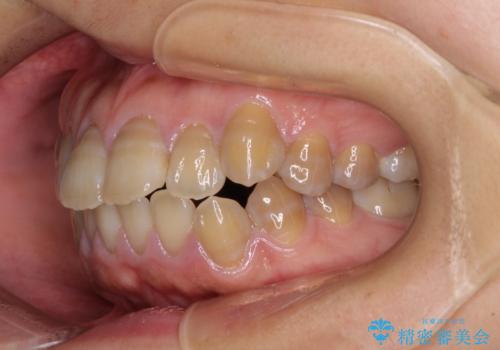

- 口元の突出感を気にして来院された患者様です。

上下前歯が著しく前突している状態であったので、上下左右の第1小臼歯4本を抜歯し、ワイヤー装置にて矯正治療を行うこととしました。

4本の歯を抜歯したことで、飛び出していた口元が引っ込み、横顔が大きく改善されました。